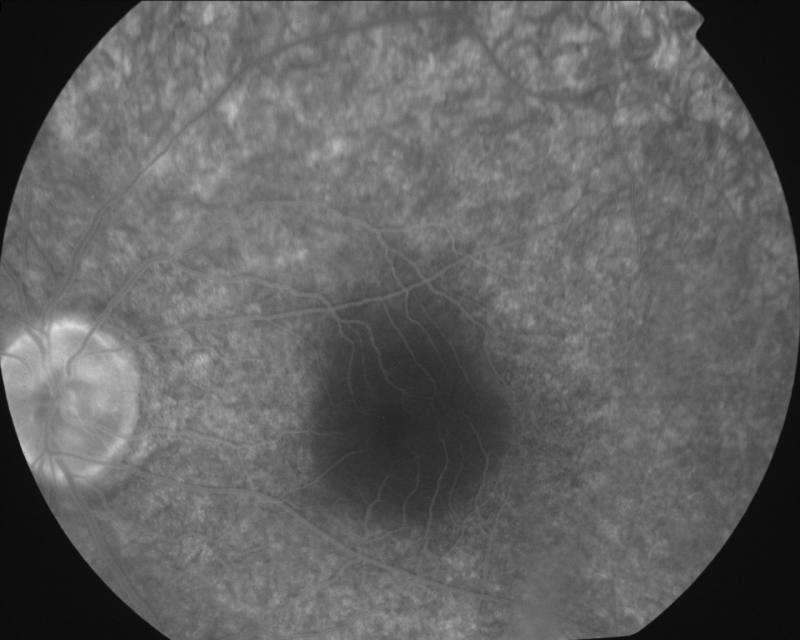

2004032205\22-03-2004

IM000036.JPG